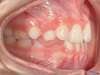

Chevauchement sévère. Traitement multibague sans extraction.

Avant

Après